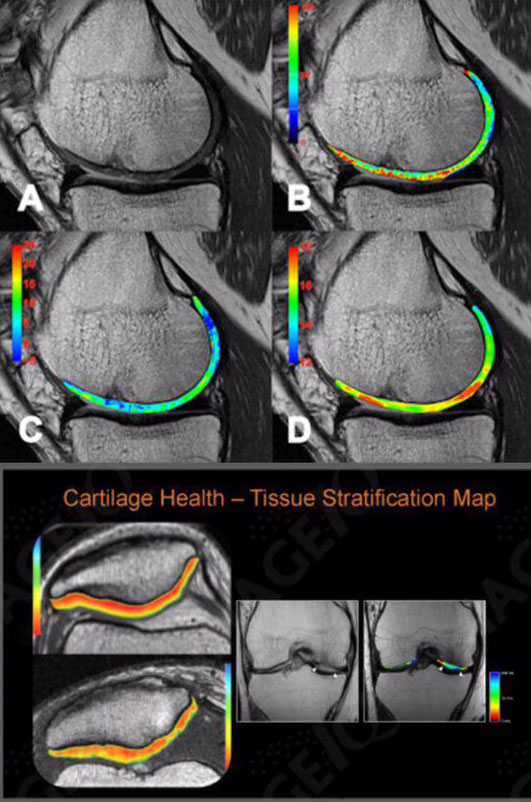

سکانس نقشه برداری T2 می تواند به تشخیص تغییرات در محتوای آب و کلاژن غضروف کمک کند . این توالی به صورت گسترده در بررسی آرتروز استفاده میشود و برای تشخیص بیماری و درمان تغییرات مربوط در غضروف مفصلی، کمک کننده میباشد.

توانائی تصویر برداری از غضروف های سطح مفصلی را امکان پذیر می سازد و در صورت بروز هر گونه تغییرات مفاصل ( DJD ) و استحاله غضروفهایHyalin کاملا قابل تشخیص میباشد .

با استفاده از این روش می توان آسیب های ناشی از استئو آرتریت را در مراحل اولیه و به صورت کاملا غیر تهاجمی و بی ضرر آشکار نموده و تدابیر لازم جهت کند نمودن روند بیماری را به کار بست .